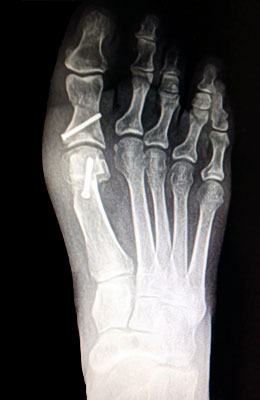

Before

After

Osteotomy Bunionectomy, Hammertoe Correction and Plantar Plate Repair after

Osteotomy Bunionectomy, Hammertoe Correction and Plantar Plate Repair

Ziba is a 67-year-old female with years of foot pain. Her bunion was so severe she had placed a lot of weight on her 2nd and 3rd toes which had become totally dislocated (as shown in x-rays). Ziba required an osteotomy bunionectomy, hammertoes corrections with our Ossio™ implant and metatarsal phalangeal joint relocation and plantar plate repair. Ziba was allowed to place weight on her foot right after surgery and was back in shoes at 8 weeks. An amazing result considering how difficult toe relocation can be. After picture taken immediately following surgery.